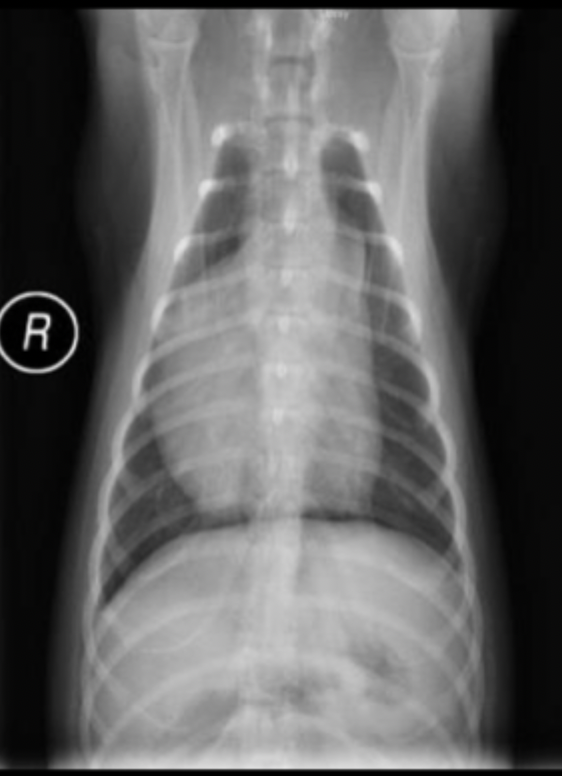

What can be seen in these cat radiographs?

Nothing, these radiographs are normal